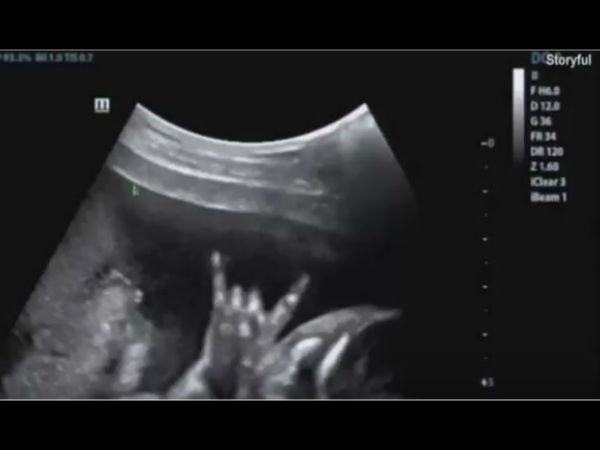

जब कोख में बच्चे ने दिया रॉक स्टार लुक, देखने वाले रह गए दंग, VIDEO वायरल

गर्भवती महिला के गर्भ में बच्चे की जो तस्वीर दिखी उसे देखकर सब दंग रह गए।

वो अपने आने वाले बच्चे को लेकर बेहद उत्साहित थी। डॉक्टर ने उसका अल्ट्रासाउंड किया तो दंग रह गई। फिर मेकेली ने भी उसे देखा और वो भी हैरान रह गई। अल्ट्रासाउंड के दौरान उसका बच्चा रॉक ऑन जेश्चर में दिखा। वो रॉक स्टार जैसे अपने हाथ की ऊंगलियों को किए हुए हाथ उठा रखा था, मानो कहने की कोशिश कर रहा हो कि अब बस वो बाहर आने वाला ही है।

मेकेली ने अपने रॉक स्टार बच्चे की तस्वीर सोशल मीडिया पर डाल दी, जो तेजी से वायरल हो गई। लेकिन कई लोगों ने कहा कि वो फेक फोटो है। इस बात को साबित करने के लिए नर्स ने फेसबुक पर अल्ट्रासाउंड का वीडियो पोस्ट कर दी और ये क्लेरिफाई भी किया कि वो एक्टिविटी रियल थी ना कि फोटोशॉप्ड। लोग इस वीडियो को देखकर हैरान हो रहे है। आप भी देखिए ये वीडियो...